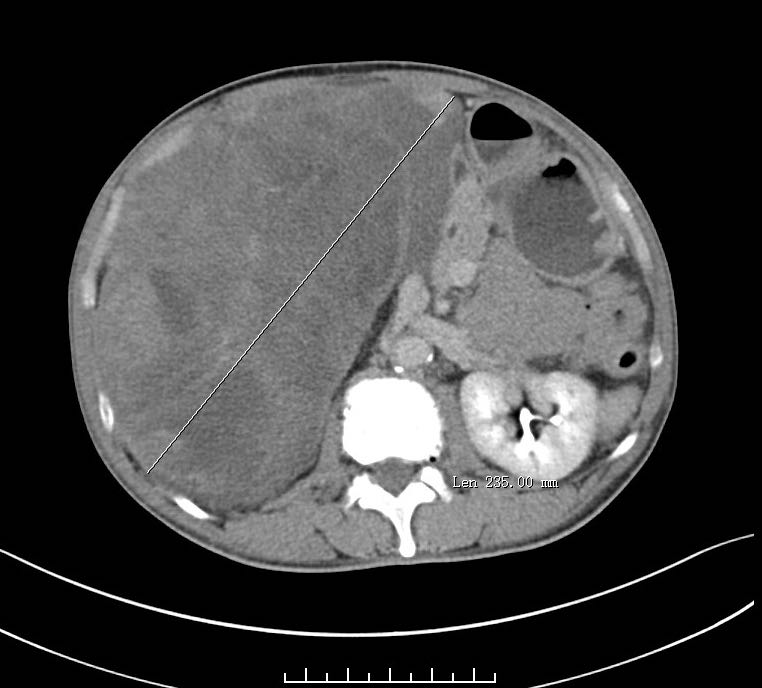

高难度巨大腹膜后肿瘤一例成功完成

图片尺寸780x1040